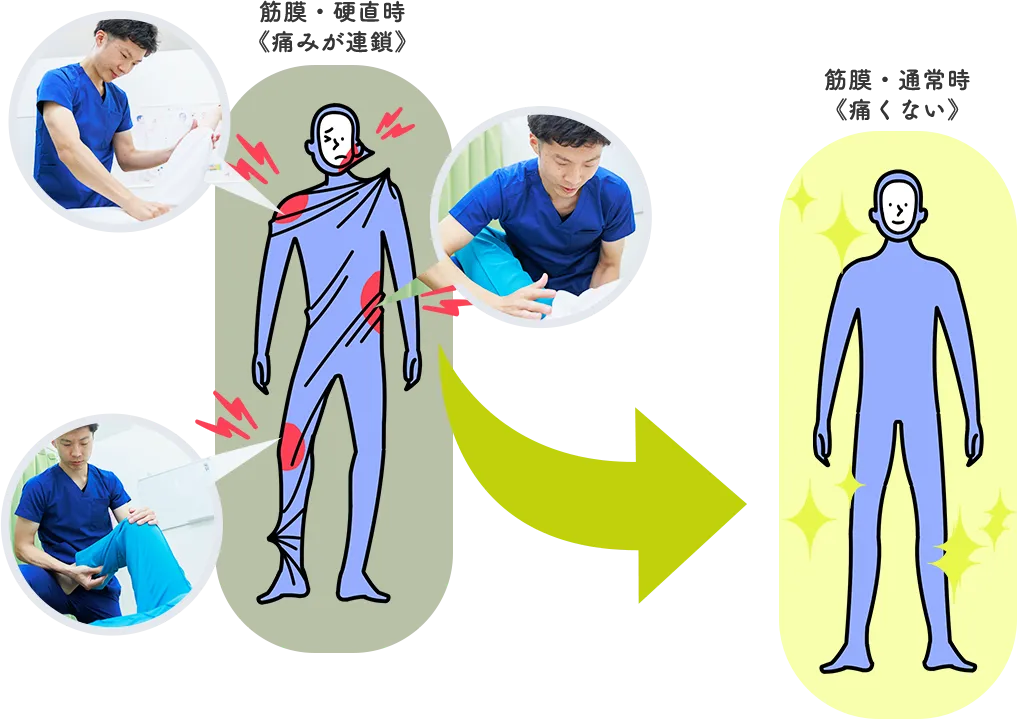

- 腰痛

- 股関節の違和感

自分の姿勢や癖を指摘してもらいエビデンスに基づいた説明、施術をしてもらうことで納得し改善も実感できました。

自分の姿勢や癖を指摘してもらいエビデンスに基づいた説明、施術をしてもらうことで納得し改善も実感できました。